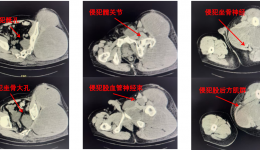

• 软骨肉瘤,虽罕见,但切莫大意

软骨肉瘤,虽罕见,但切莫大意

近日,日照55岁的王先生出现右膝部疼痛2个月,而且病情逐渐加重,影响站立及行走,生活质量下降,在当地医院进行影像学检查后考虑股骨恶性肿瘤,推荐到齐鲁医院青岛院区,经过骨科中心学科带头人李建民教授接诊后查体、影像学评估及穿刺病理,最终...